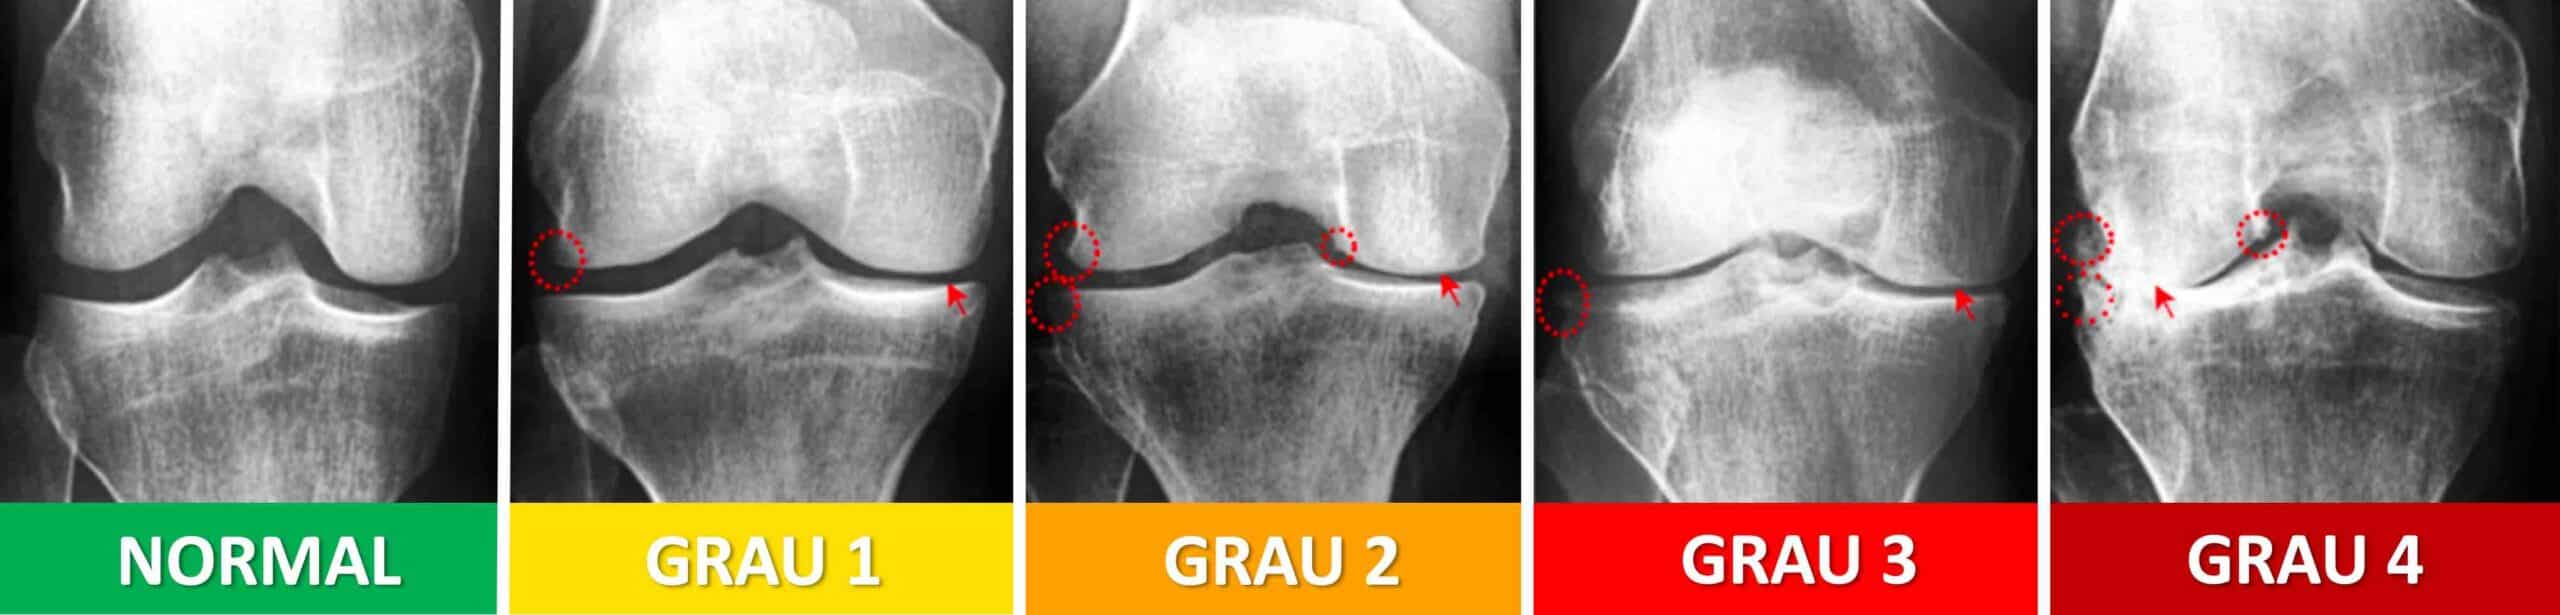

A artrose é a doença que mais acomete a articulação do joelho e é uma das causas mais comuns de afastamento do trabalho em todo o mundo. A doença, também conhecida como osteoartrite ou gonartrose, é caracterizada pela degeneração e/ou desgaste da cartilagem. Cartilagem é o tecido branco e brilhante que recobre os ossos dentro das articulações sinoviais. Dentro do joelho existe cartilagem revestindo os côndilos do fêmur, o platô tibial e a patela. A função da cartilagem é prover uma superfície lisa e lubrificada para que os ossos em contato dentro da articulação deslizem uns sobre os outros para que haja movimento articular. A cartilagem é um tecido histológico muito delicado. Por diferentes causas, a cartilagem pode se degenerar, expondo o osso subcondral. Em casos mais avançados da doença, existe contato direto de osso com osso. Dor, inchaço, crepitação, deformidade e limitação funcional são sintomas de um joelho com artrose. A dor é o sintoma mais importante. É a dor que realmente compromete a qualidade de vida do paciente. As características da dor da artrose do joelho variam e dependem do estágio da doença.

A dor da artrose do joelho ocorre devido ao desgaste estrutural e à inflamação provocados pela doença. A cartilagem em si não dói porque é um tecido aneural, ou seja, sem nervos. A dor surge quando o osso subcondral fica exposto e sofre microfraturas pelo impacto direto de osso com osso, além da liberação de detritos celulares e substâncias inflamatórias dentro da articulação que irritam a membrana sinovial, gerando sinovite crônica que provoca inchaço ( derrame articular ) e ativação de receptores sensíveis à dor. A composição do líquido sinovial fica alterada, com diminuição de ácido hialurônico e concentração de substâncias inflamatórias. Os condrócitos, que são as células da cartilagem, entram em sofrimento. A matriz extracelular da cartilagem começa a se desmanchar. O corpo tenta estabilizar o compartimento colapsado com a formação de osteófitos, que também provocam inflamação e dor ao seu redor. O desgaste mecânico se transforma num ciclo constante de inflamação, com dor, inchaço e sofrimento sensorial permanente. A dor da artrose varia, dependendo da fase da doença: artrose inicial, artrose moderada e artrose avançada. Leva-se muito tempo, geralmente vários anos, para a artrose evoluir da fase inicial até a fase avançada.